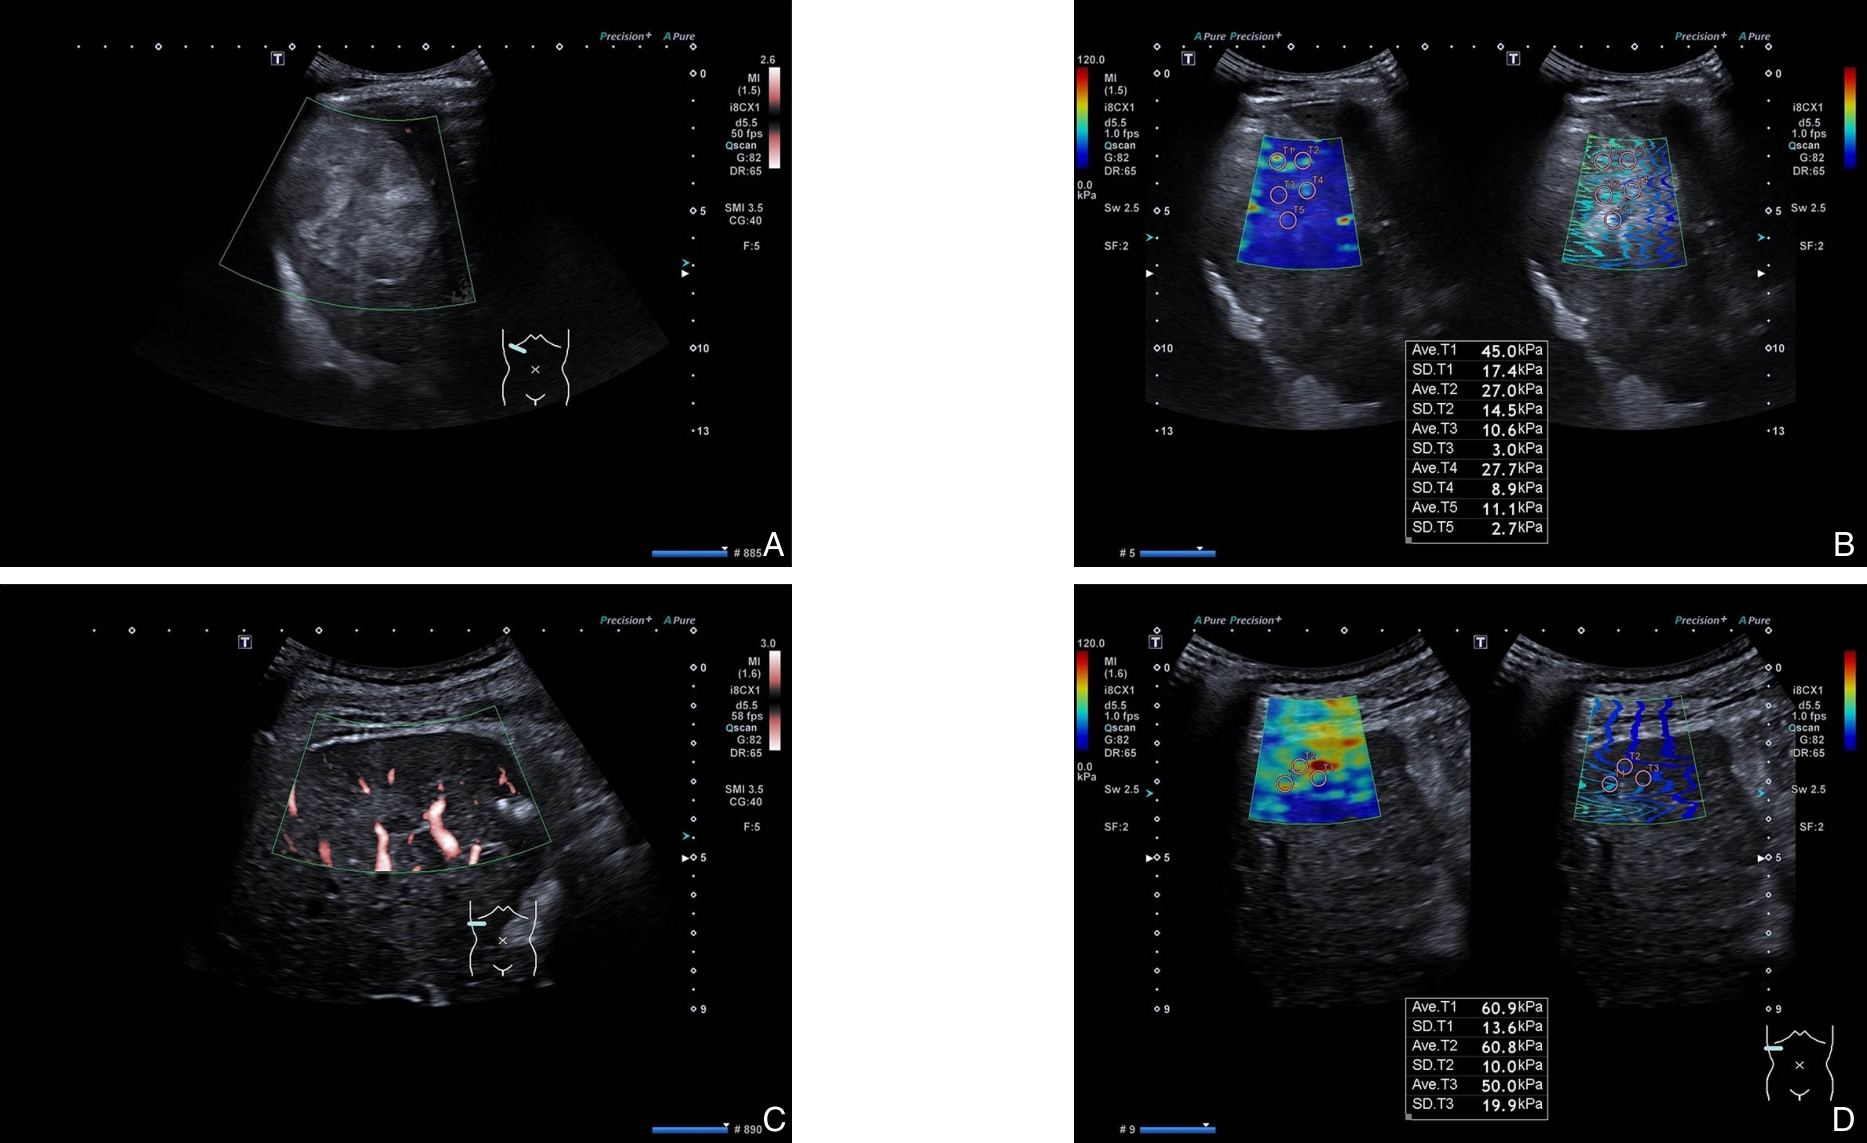

背景与目的 中晚期肝癌患者接受经导管动脉化疗栓塞(TACE)联合射频消融(RFA)序贯治疗后复发率仍较高,术前缺乏可靠的风险分层工具。本研究基于超微血管成像(SMI)与剪切波弹性成像(SWE)构建多模态超声联合机器学习模型,并结合SHAP算法进行可解释性分析,旨在预测中晚期肝癌患者TACE-RFA序贯治疗后的复发风险。方法 回顾性纳入2022年6月—2024年6月215例BCLC B/C期肝癌患者,按7∶3比例分为训练集(n=150)与测试集(n=65)。收集临床资料、生化指标及SMI、SWE超声特征。采用随机森林、支持向量机及极限梯度提升(XGB)进行变量重要性排序,结合交集筛选及双向逐步Logistic回归确定独立预测因子。构建7种机器学习模型,通过10折交叉验证优化参数。以曲线下面积(AUC)、敏感度、特异度、Brier评分及决策曲线分析(DCA)评价模型性能,并利用Tree SHAP解释模型输出。结果 术前肿瘤最大径、甲胎蛋白(AFP)、最大弹性模量(Emax)、弹性比值(Eratio)及血管形态为独立预测因子。XGB模型在训练集与测试集中的AUC分别为0.989和0.959,Brier评分分别为0.034和0.056,DCA显示其在较宽阈值范围内具有最佳净收益。SHAP分析表明,高Eratio、高AFP、血管形态不规则及肿瘤最大径较大显著增加复发风险,而较低Emax与复发风险降低相关。结论 基于SMI-SWE多模态超声构建的XGB模型可较准确预测中晚期肝癌患者TACE-RFA序贯治疗后的复发风险,具有良好的临床应用潜力。SHAP分析增强了模型的可解释性,为术前个体化风险评估和治疗决策提供了量化依据。

2026,35(2):323-333, DOI: 10.7659/j.issn.1005-6947.250439

Abstract: